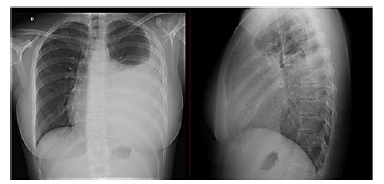

Paciente do sexo feminino, de 25 anos de idade, estudante universitária, tinha história de asma intermitente na infância, sem necessidade de uso de broncodilatador havia quase 10 anos e uso diário de medicações. Compareceu à emergência relatando mal-estar, febre e tosse produtiva havia 12 dias. Nos últimos 2 dias, tinha havido piora da tosse, febre persistente apesar do uso de antitérmicos, inapetência e início de dor torácica próxima ao mamilo direito, principalmente à inspiração profunda. Ao exame físico, havia diminuição do murmúrio vesicular no terço inferior do hemitórax esquerdo e macicez à percussão. O hemograma indicou leucocitose com 12% de formas jovens. A imagem a seguir mostra o Raio X de tórax da paciente.